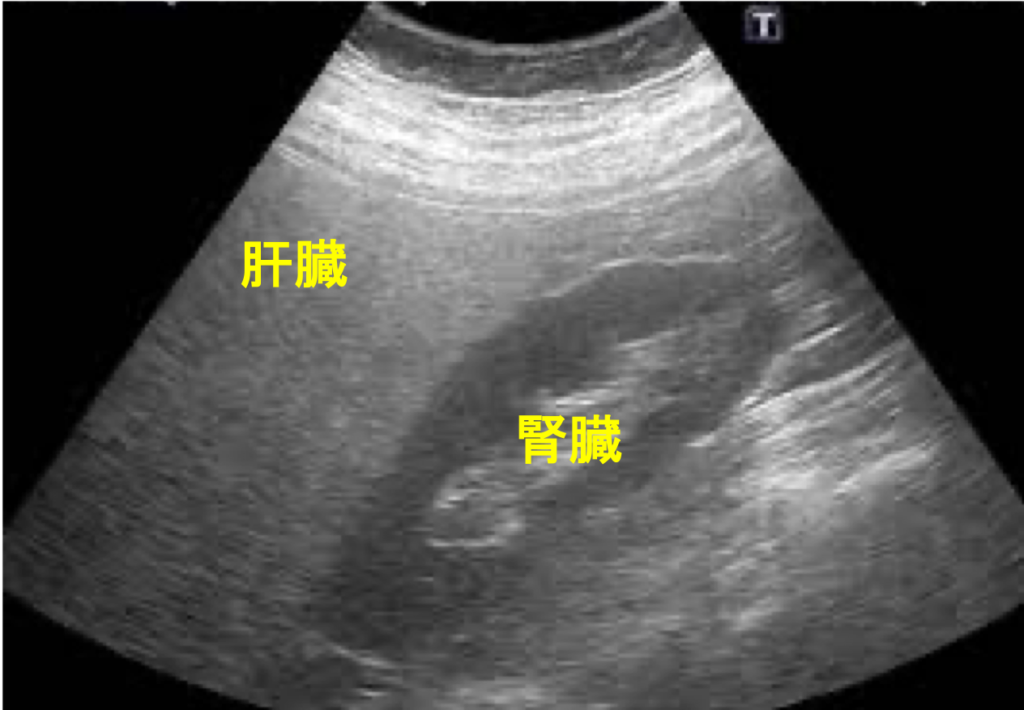

小野クリニックでは、血液検査や超音波検査(エコー)を用いて、「なぜ肝臓の数値が悪いのか」を突き止め、患者様一人ひとりのライフスタイルに合った治療方針をご提案します。